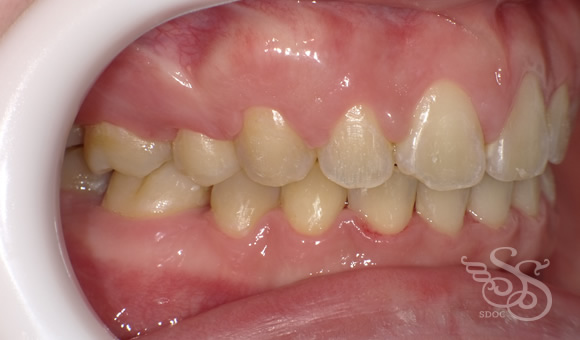

右側:術後

将来、ブリッジやインプラントにするより

いま矯正した方が、何倍ものメリットが得られます。

動的治療期間 2年4ヶ月でした。